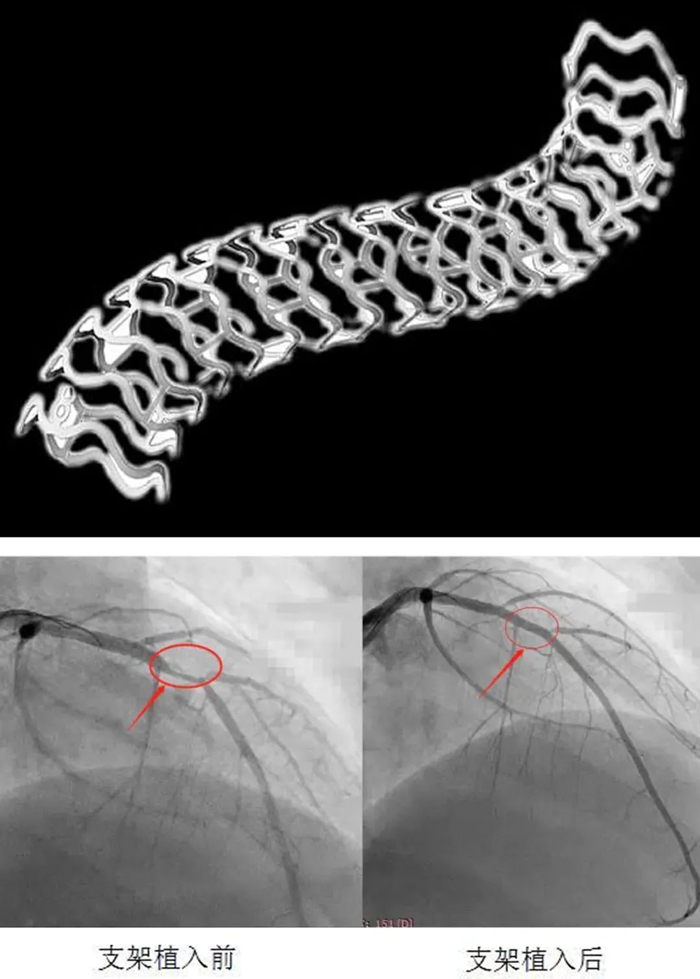

患者入院后完善術前準備,給予冠脈造影檢查示:右冠脈支架通暢,未見狹窄,左冠脈前降支近端可見90%局限性狹窄。考慮患者年輕,病變為A型病變,參考患者家人意愿,決定給予患者可降解支架植入。

在郭明主任指導下,心內科介入團隊先對病變處給予普通球囊及切割球囊充分預擴張,再給予血管內超聲(IVUS)精確測量血管內徑,選擇3.0×28生物可吸收支架,以8atm×30s釋放支架,再以血管內超聲(IVUS)對支架貼壁情況給予評估后,以3.0后擴球囊給予“修飾”,IVUS再次評估,貼壁良好,手術順利結束。